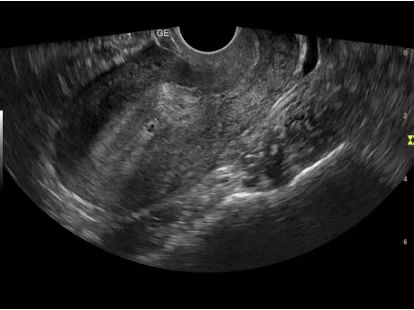

高清病例展示图:

ct什么牌子的好【喜讯】瑶医医院影像科大型CT设备顺利开机并投入使用_https://www.jmylbn.com_新闻资讯_第13张

◆ 腔内探头子宫图像 ◆